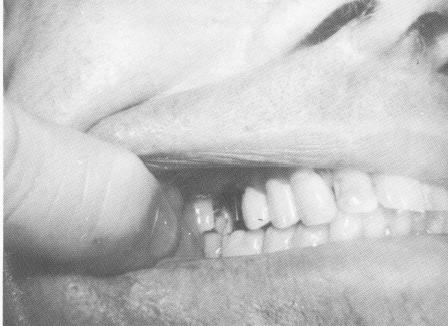

Fig. 8-48. The implant post extending from the fibromucosal tissue in the endentulous area is seen between the bicuspid and molar teeth. Notice the mesiocclusal preparation on the molar.

4 Upper implant post extends from fibromucosa in posterior area